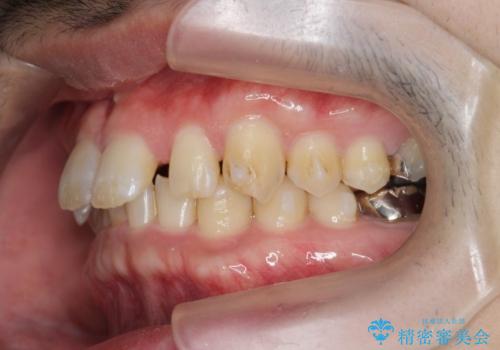

ディープバイトのマウスピース矯正

- 飛び出してしまい、隙間のある前歯をきれいに並べたい、と矯正治療を希望され来院されました。

上顎前歯を後方に引き、隙間を閉じるためには下顎前歯の絶対的な圧下を行い、深い噛み合わせを改善することが必要です。

圧下は歯の動きの中でも難しい動きの一つで時間がかかることが多いです。

前歯でチューイーをしっかり噛み、咬合圧を伝えたことで下顎前歯が圧下し、上顎前歯の隙間を閉じることができました。